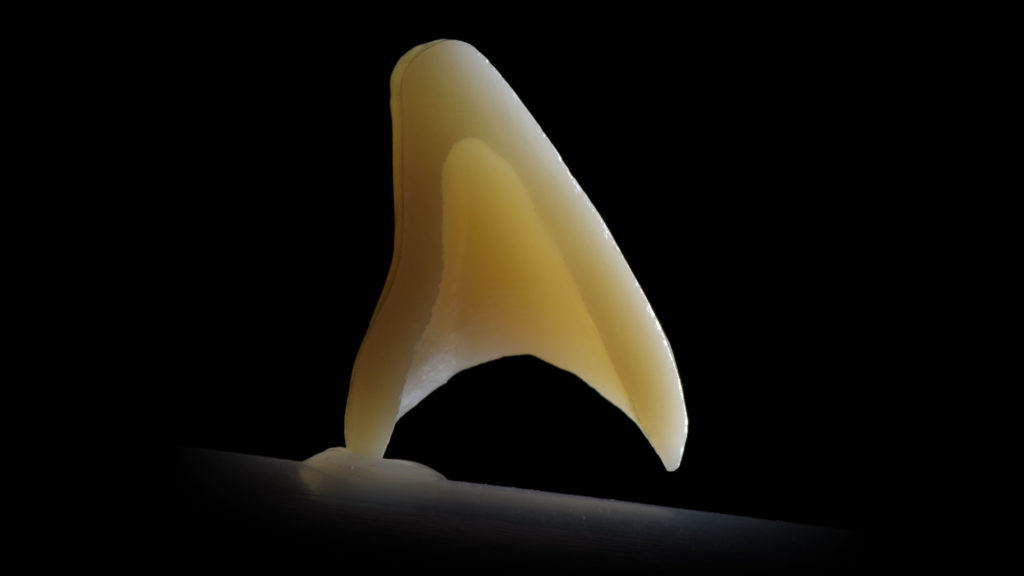

Die Verblendkeramiken von Kuraray Noritake zeichnen sich dadurch aus, dass sie extrem vielseitig sind. Ob für die traditionelle Schichttechnik oder das „Bemalen“, mit den Systemkomponenten lassen sich qualitativ hochwertige Versorgungen auf ästhetisch höchstem Niveau erzielen. Fälle, die klassisch mit Schichtkeramik gelöst werden sollen, erfordern ein nicht zu opakes Dentin, das mit einer opaleszierenden Luster-Masse überzogen wird (Abb. 1).

Anatomisch reduzierter Dentinkern

Zirkonoxid wird in all den in diesem Artikel beschrieben Variationen als dentaler „Kern“ verwendet. Dieser Dentinkern wird, je nachdem, welches der genannten Zirkonoxide zum Einsatz kommt und wofür, mit einem speziellen internen Design versehen. Dadurch lässt sich zum einen auf die individuellen Vorgaben der zu rekonstruierenden Situation besser eingehen (etwa Alter, Farbe und Opaleszenz), und zum anderen dem Anspruch an eine höhere Festigkeit gerecht werden. Dieses Gerüst wurde so designt, dass die Zahnform mit Schichtkeramik (Dentin- und Luster-Massen) komplettiert wird (Abb. 5).